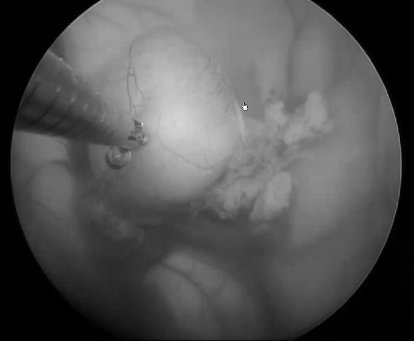

手术采用神经导航系统确定最佳穿刺点。操作步骤包括:电凝处理脉络丛及囊壁血管,切开囊肿壁并吸除内容物,使用抓钳将囊膜牵拉至侧脑室,特别注意处理对侧脉络丛与囊肿粘连部位,完全游离前需电凝并切断粘连的脉络丛。

手术中使用LOTTA脑室镜(Karl Storz SE & Co.KG)配合穿刺针进入侧脑室额角。通过侧方通道采用微型抓钳提起囊膜,显露囊肿与第三脑室脉络膜组织的连接部位。经主工作通道置入双极电凝探头处理血管,再用显微剪刀离断囊蒂,完成囊肿切除。